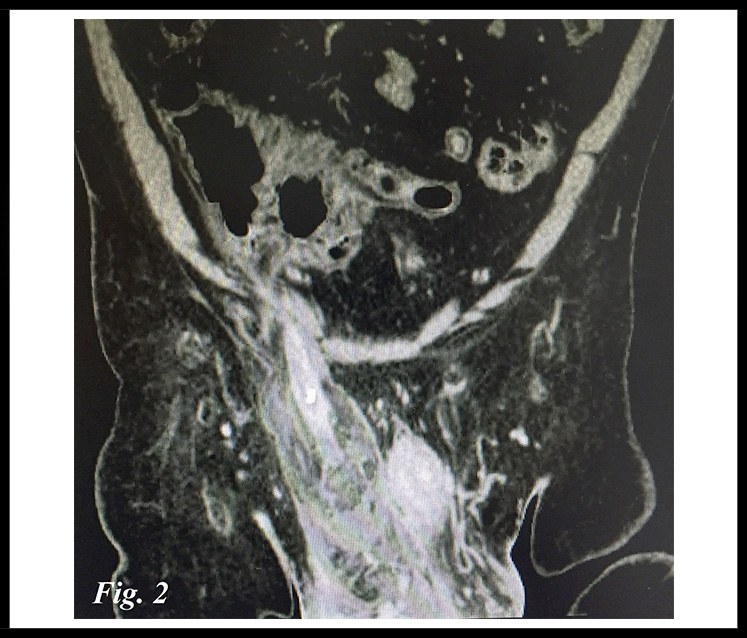

Se completó el diagnóstico mediante un TAC con contraste intravenoso que mostró el apéndice vermiforme engrosado, con origen en el ciego extendiéndose hacia el canal inguinal. (Figura 1 y 2)

Figura 2.